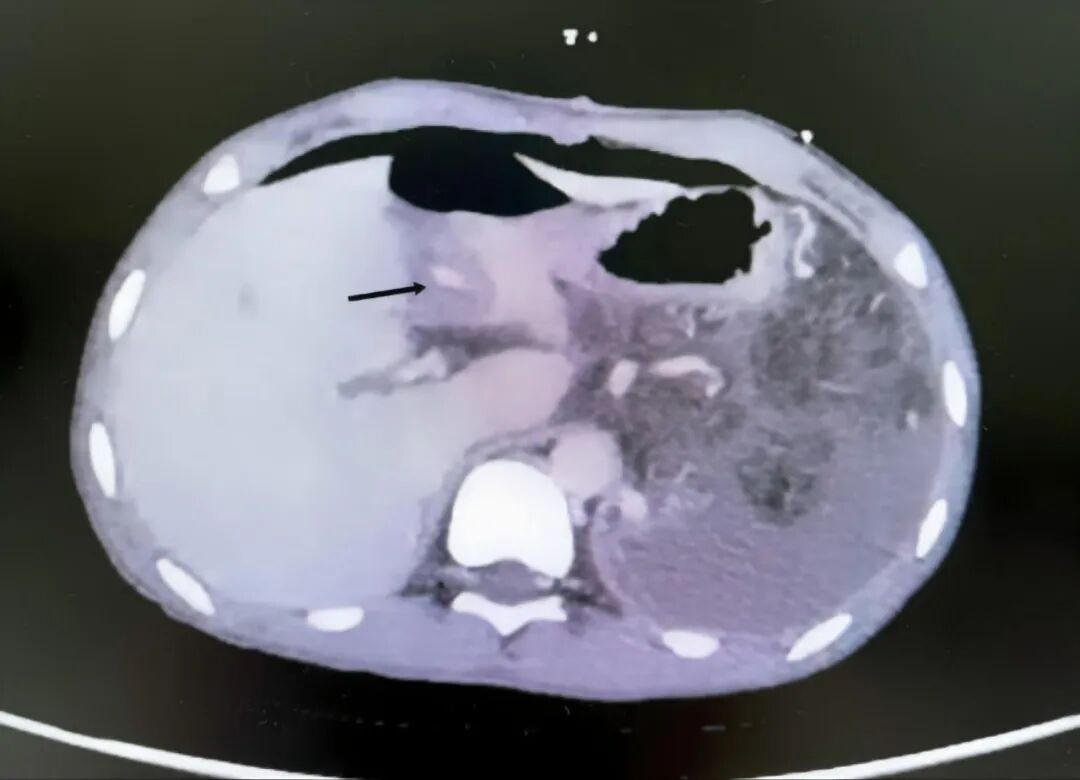

术后,门脉高压诊疗团队给予精细化管理,两次复查增强CT、一次超声均显示搭桥血管通畅,无门静脉血栓形成,小李的血红蛋白水平稳定在80g/L以上,血小板计数恢复至290×10⁹/L以上。术后第8天,小李已能正常进食、自主下地活动,恢复情况良好,顺利办理出院手续,出院后需继续口服抗凝药物治疗。

图2 术后CT图像显示Rex搭桥血管通畅